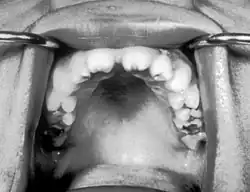

| Notched incisors known as Hutchinson's teeth which are characteristic of congenital syphilis | |

Congenital syphilis that is diagnosed after 2 years of age, either because it was not diagnosed earlier or because it was incompletely treated, is classified as late congenital syphilis.[19] The signs of late congenital syphilis tend to reflect early damage to developing tissues that does not become apparent until years later,[20] such as Hutchinson's triad of Hutchinson's teeth (notched incisors), keratitis and deafness.[21][22]

- Blunted upper incisor teeth known as Hutchinson's teeth, or mulberry molars[7]

- Hutchinson's triad, a set of symptoms consisting of deafness, Hutchinson's teeth (centrally notched, widely spaced peg-shaped upper central incisors), and interstitial keratitis (IK), an inflammation of the cornea which can lead to corneal scarring and potential blindness[27]